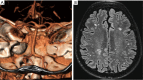

Figure 3

Brain imaging in LOPD. (A) CT-scan showing a vertebral dolichoectasia in a 64-year-old LOPD female; (B) T2 weighted scan showing a lacunar encephalopathy (Fazekas score 2). LOPD, late onset Pompe disease.